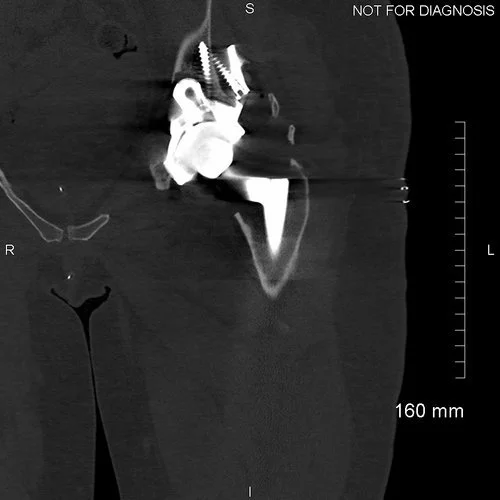

Coronal CT - This is used by the surgeon and the biomedical engineer to design the custom implant specifically to the patient’s acetabular bone stock. This CT demonstrates significant loss of bone stock relating to the left hip resurfacing.

3D CT reconstruction showing the hemipelvic defect.

Implant design showing the custom acetabular implant designed around this patients bony anatomy. The blue areas highlight regions of trabecular titanium.

Coronal CT showing that the acetabular component is properly seated and the screws are within the bone.